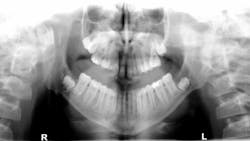

A 14-year-old male was referred to the oral and maxillofacial surgeon to evaluate his lower third molars, each of which appeared on the panoramic radiograph to have significant well-circumscribed, expansile radiolucencies around the impacted teeth.

Removal of the lower third molars and the associated cystic lesions produced an expected histopathologic diagnosis of bilateral keratocystic odontogenic tumors. Because of the high suspicion of this diagnosis, surgery included aggressive removal of the lesions with peripheral ostectomy and treatment with Carnoy's solution.